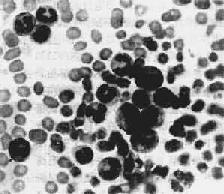

毛細胞性白血病1.普通光學顯微鏡觀察:胞體稍大,直徑約12μm~20μm,形態不一,可見到圓型、橢圓型或多角型,胞漿周邊不規則呈鋸齒狀或偽足突起,有時呈細長毛髮狀伸出;細胞核呈橢圓型或凹陷核裂;染色質緻密或疏鬆,偶見核仁;胞漿中等量,瑞氏染色呈天藍色。

2.相差顯微鏡觀察:用相差顯微鏡觀察新鮮標本對毛細胞更易辨認,在細胞分散充分的標本中可見細長毛髮狀的胞漿突起,有時可見到毛的活動以及毛相交的吸附現象。

3.電子顯微鏡觀察:掃描電鏡觀察可見細胞表面有較多散射的細長毛狀突起,最長可達4μm,延伸的毛有交叉現象;另一部分細胞表面呈皺摺狀突起。透射電鏡為另一種識別毛細胞的手段,除表面有偽足突出外,胞漿內可見核糖體板層複合物(RLC),高爾基體發達。